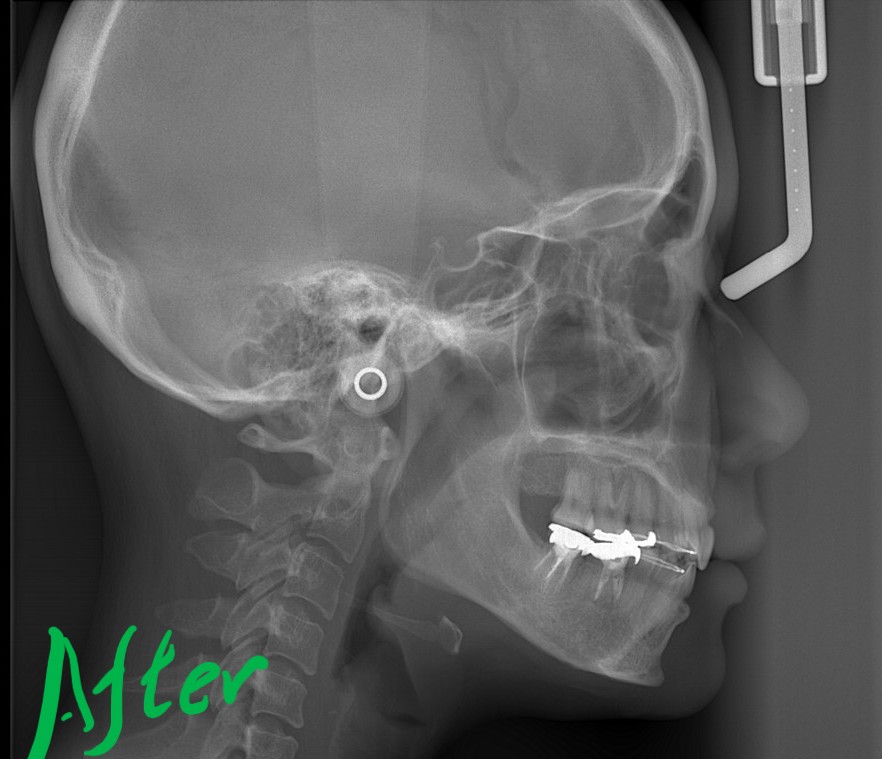

【After】

矯正後の状態をレントゲン写真で確認すると、

横顔や口元は患者さんの希望通りにスッキリして、満足してもらえました。

術前も口元にEラインを引くことが出来ました(レントゲン参照)が、お顔全体のバランスという意味で、同じEラインであっても術前と術後ではスッキリ感が異なります。

なお結局、ガミースマイルの改善は行わないまま治療を終了しました。

この方の場合、美容外科にてオトガイ形成術の既往がありました。 そのためお顔のバランスを考えた時に前歯の引っ込め具合をちょっと加減しました。 それが無ければ、もっと積極的に前歯を引っ込めて(いわゆる)顎を作るプランを実行したと思われます。